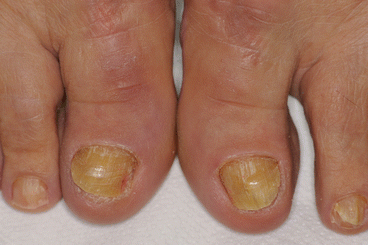

Subungual hyperkeratosis results from deposition and accumulation of desquamated cells underneath the nail plate. This leads to detachment of the nail plate from the nail bed. The degree of this detachment depends upon the level of psoriatic activity present. Subungual hyperkeratosis in nail psoriasis is typically characterized by a silvery-white discoloration as opposed to the typical yellow, greasy appearance seen in onychomycosis, but this is not always the case [1, 4] (Fig. 14.2).

Fig. 14.2

Nail psoriasis presenting with subungual hyperkeratosis, onycholysis, and yellow discoloration